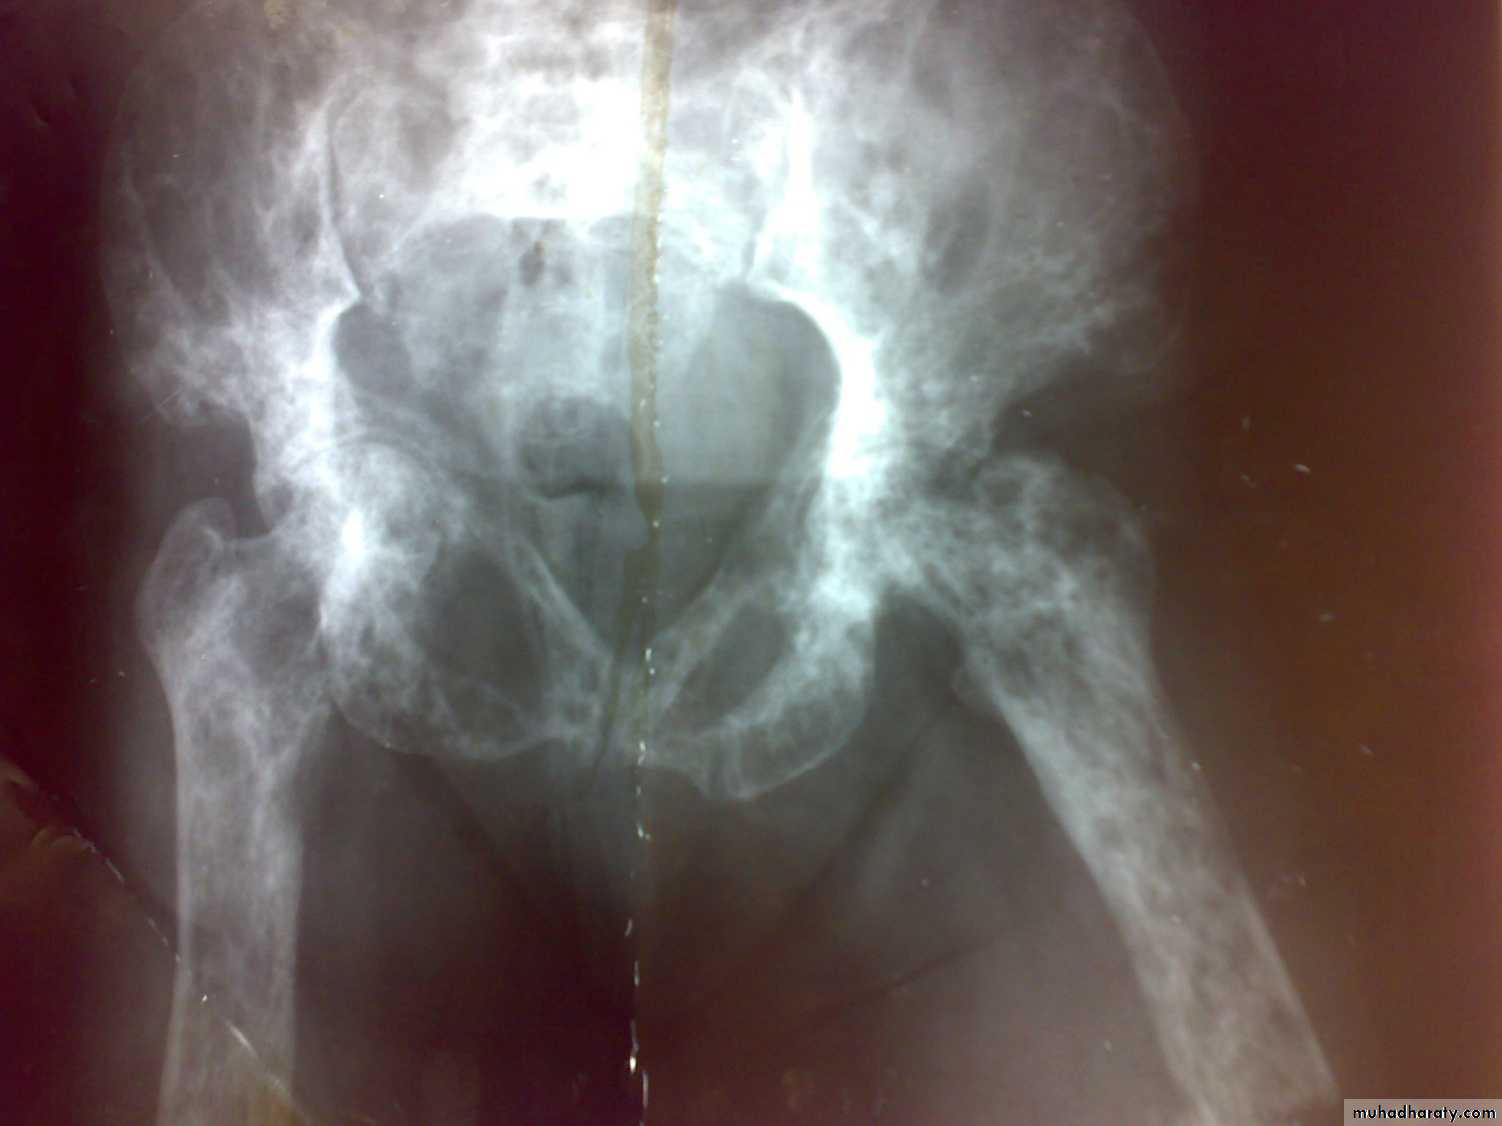

Wolff’s Law: Wolff’s Law is beautifully demonstrated

in the trabecular pattern at the upper end of the femur.The thickest trabeculae are arranged along the trajectories

of greatest stress.